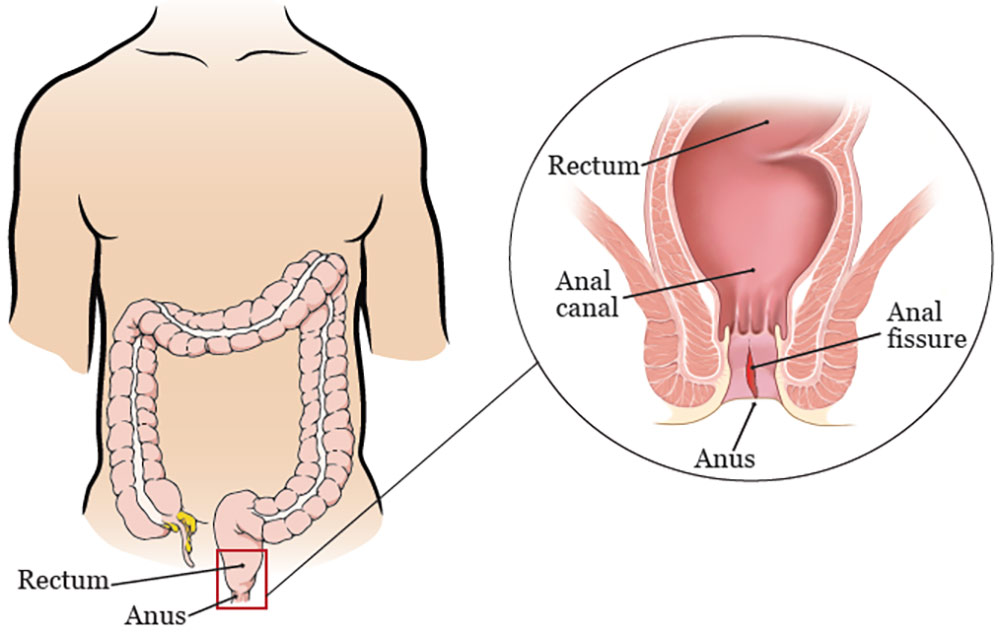

شقاق مقعدی یک نقص سطحی در پوست است که در قسمت خطوط دندانه ای این ناحیه قرار دارد و یکی از علت مراجعه به اتاق اورژانس می باشد. شکاف های مقعدی در بزرگسالان و کودکان بسیار شایع است و افرادی که سابقه یبوست دارند، مکررا این وضعیت را تجربه می کنند. این پارگی ها می تواند شقاق حاد (کمتر از 6 هفته) یا شقاق مزمن (بیش از 6 هفته) باشد.

اکثر شکاف های مقعدی معمولی / اولیه در خط میانی خلفی دیده می شوند. درصد کمی از آن ها ممکن است در خط میانی قدامی رخ دهند. شکاف های غیرمعمولی / ثانویه می توانند به علت سایر شرایطی که نیاز به کار و درمان بیشتری داشته باشند، ایجاد شوند. تشخیص فیشر مقعد عمدتا بالینی است که چندین گزینه درمانی برای آن وجود دارد، از جمله مدیریت پزشکی و گزینه های جراحی.

علل شکاف های مقعد معمولا شامل یبوست، اسهال مزمن، بیماری های منتقله از راه جنسی، سل، بیماری التهابی روده، اچ آی وی، سرطان مقعد، زایمان، جراحی قبلی مقعد یا مقاربت جنسی است. به نظر می رسد بیشترین دلیل بروز این عارضه به علت عبور مدفوع سخت، عفونت های منتقله جنسی (STI) یا آسیب های مقعدی به دلیل نفوذ یک شیء است.